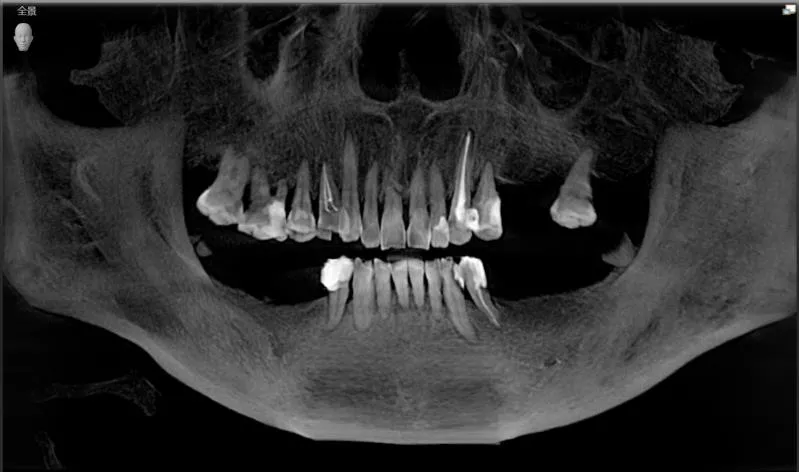

叔叔术前口内CBCT全景照

看到阿姨总是忽视自己,对自己的身体健康蛮不在乎的样子,叔叔也非常焦心。就先在海德堡联合口腔做了种植牙手术,做了4颗种植体。

曹申主任为阿姨进行了数字化的会诊,借助Sirona CBCT全景影像信息和相关修复信息为基础,借助数字化专业种植设计软件进行术前诊断和种植方案规划。